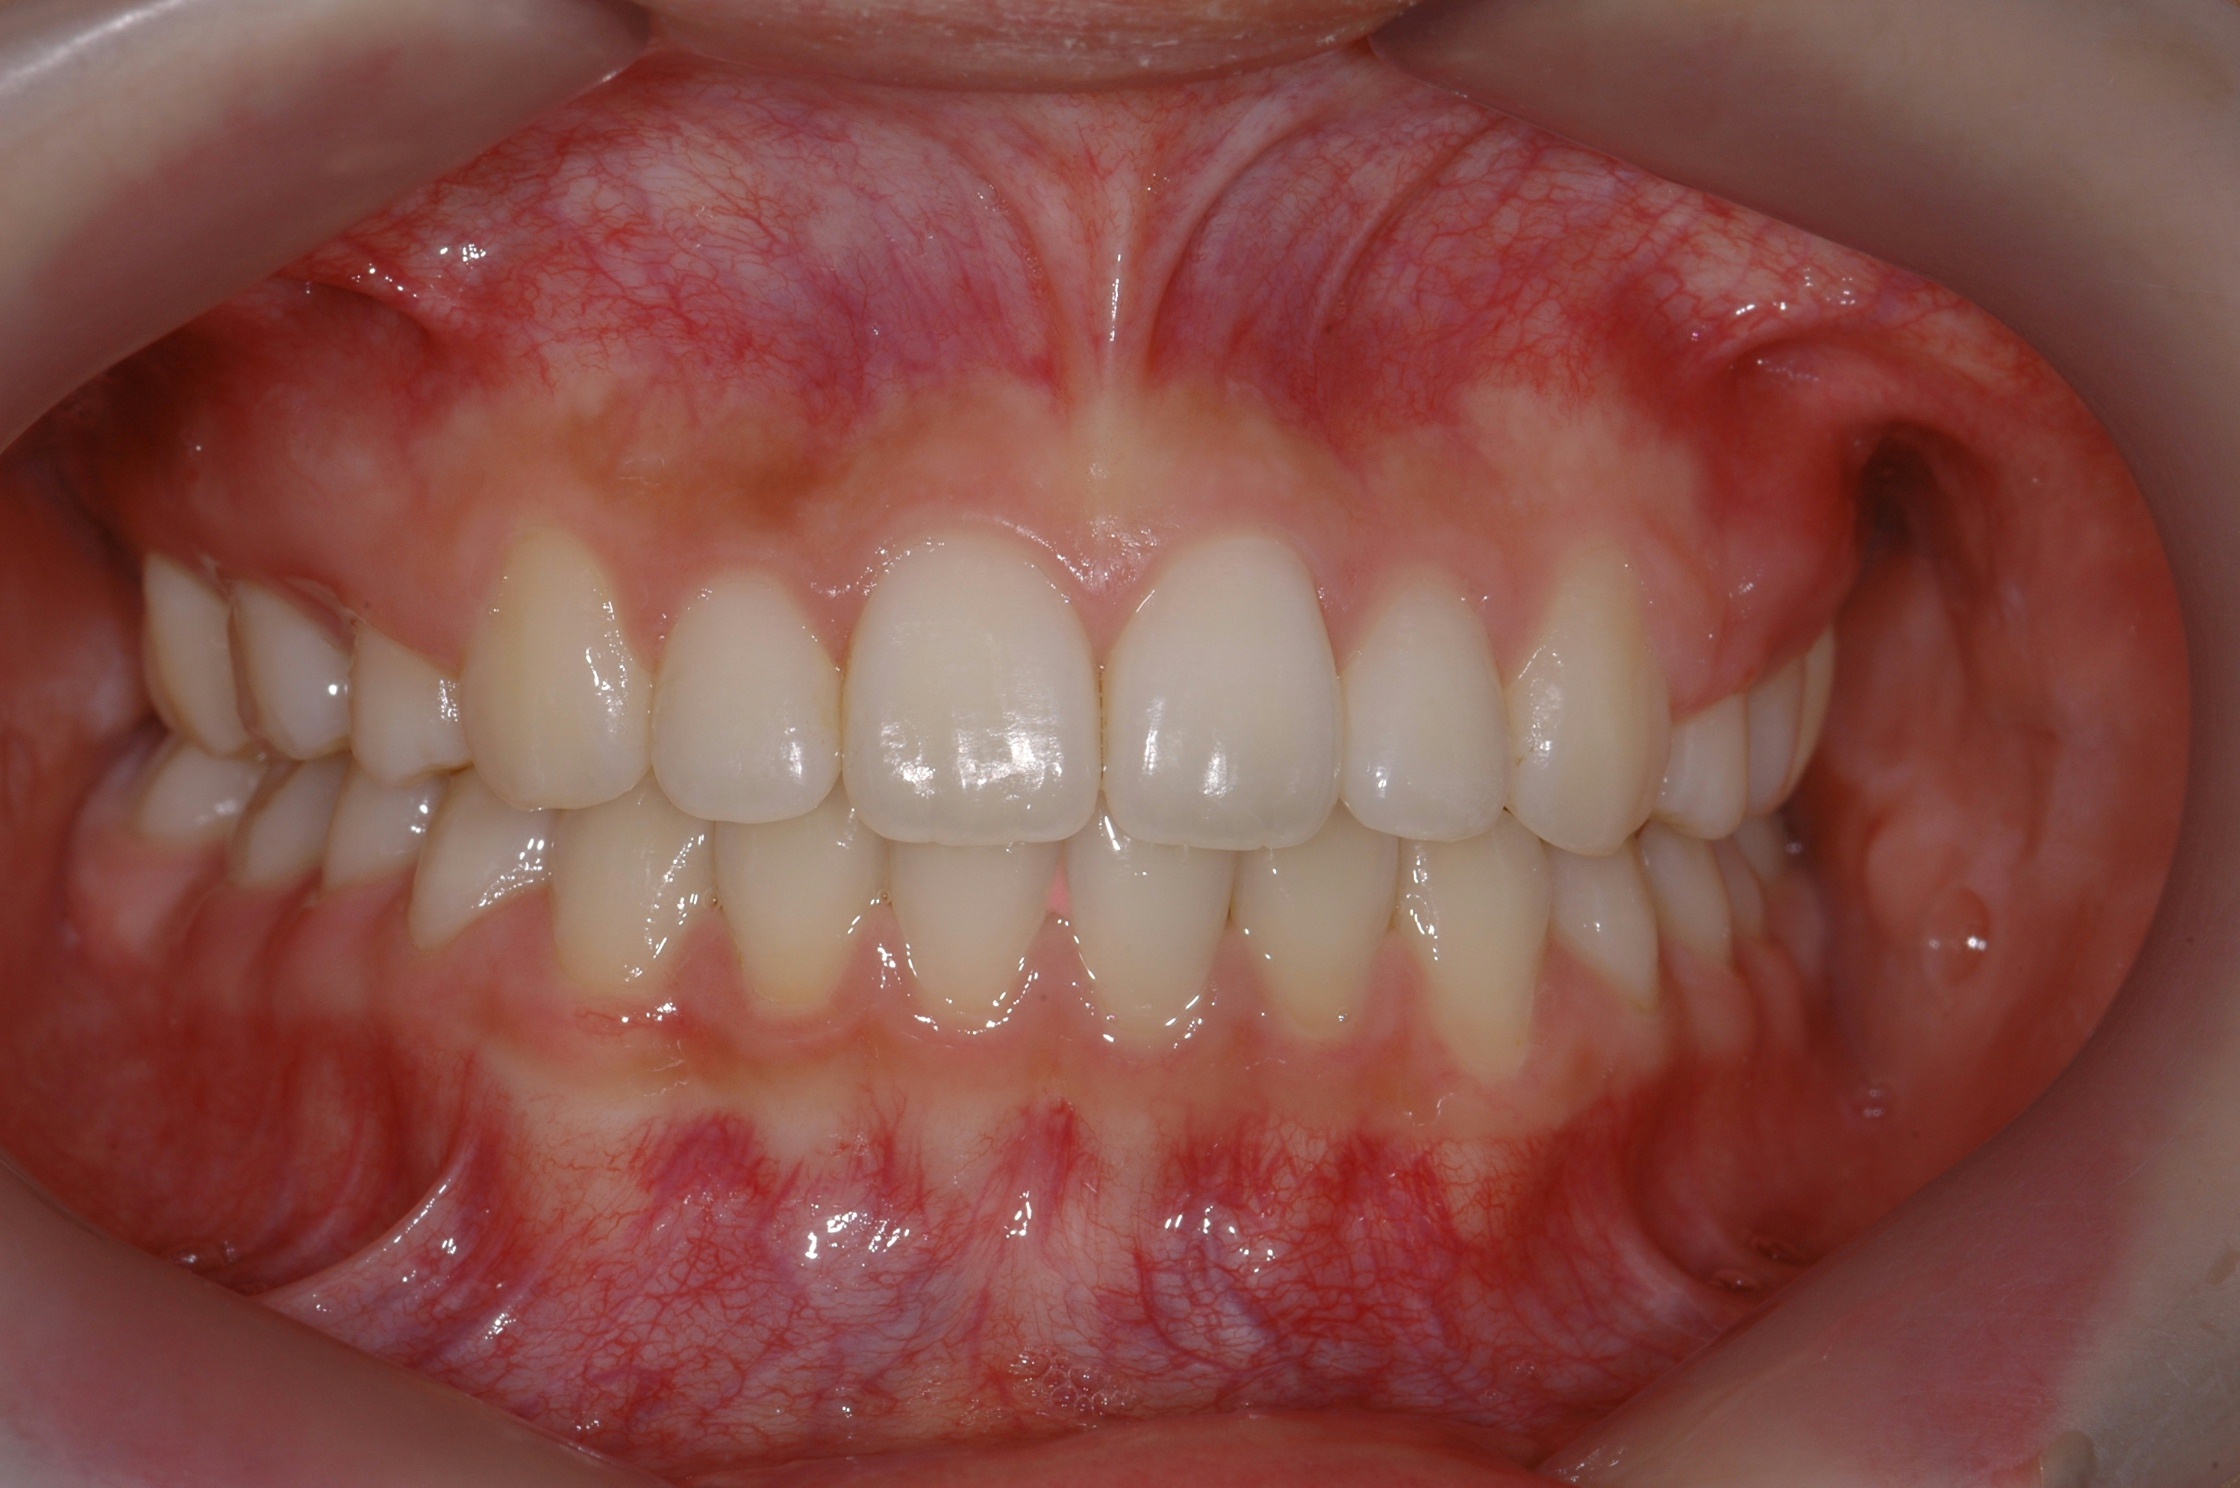

치료 전 사진입니다.